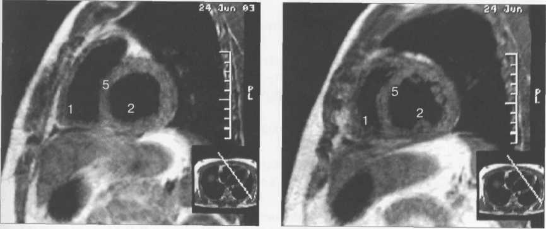

Рис. 9.51. МРТ сердца. Сечения по короткой оси левого желудочка.

Рис. 9.52. МРТ сердца. Четырехкамерные сечения.

На рис. 9.47—9.52 представлены Т1-ВИ наиболее часто используемых МР-сечений сердца.

Здесь и на рис. 9.48—9.52:

I — правый желудочек, 2 — левый желудочек, 3 — правое предсердие, 4 — левое предсердие, 5 — межжелудочковая перегородка, 6 — межпредсердная перегородка, 7 — задняя стенка левого желудочка, 8 — восходящая часть аорты, 9 — дуга аорты, 10 — нисходящая часть аорты, 11 — легочный ствол, 12 — правая легочная артерия. 13 — левая легочная артерия, 14 — верхняя полая вена, 15 — нижняя полая вена, 16 — трахея.